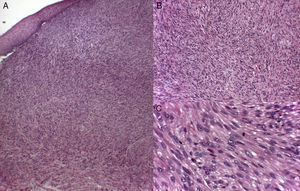

Histology recognizes 2 architectural patterns. One is a nodular pattern characterized by cellularity, cell atypia, and mitotic figures. The other is a diffuse pattern with lower cellularity and a lower mitotic index. Because cell atypia is not always evident, a histologic diagnosis should be supported by the overall architecture of the lesion (infiltrative pattern and high cellularity). It is particularly important to obtain adequate samples for histopathology, and incisional biopsies that extend below the dermis are preferred. Immunohistochemistry is an essential tool for distinguishing these neoplasms from tumors with fusiform cells and for establishing lineage11 (Fig. 2).

Histology found a mean of 11 mitotic figures per 10 HPF and Ki-67 protein expression of 30% in cutaneous tumors, 7.5 mitotic figures per 10 HPF and Ki-67 expression of 60% in subcutaneous forms, and 10.2 mitotic figures per 10 HPF and Ki-67 expression of 48% in metastatic forms. Immunohistochemical staining was positive for vimentin (>25% of cases), desmin (>50%), HHF-35 (>75%), and SMA (>75%). S100 staining was focally positive in 1 cutaneous leiomyosarcoma; CD34 staining was also positive in 1 cutaneous tumor.